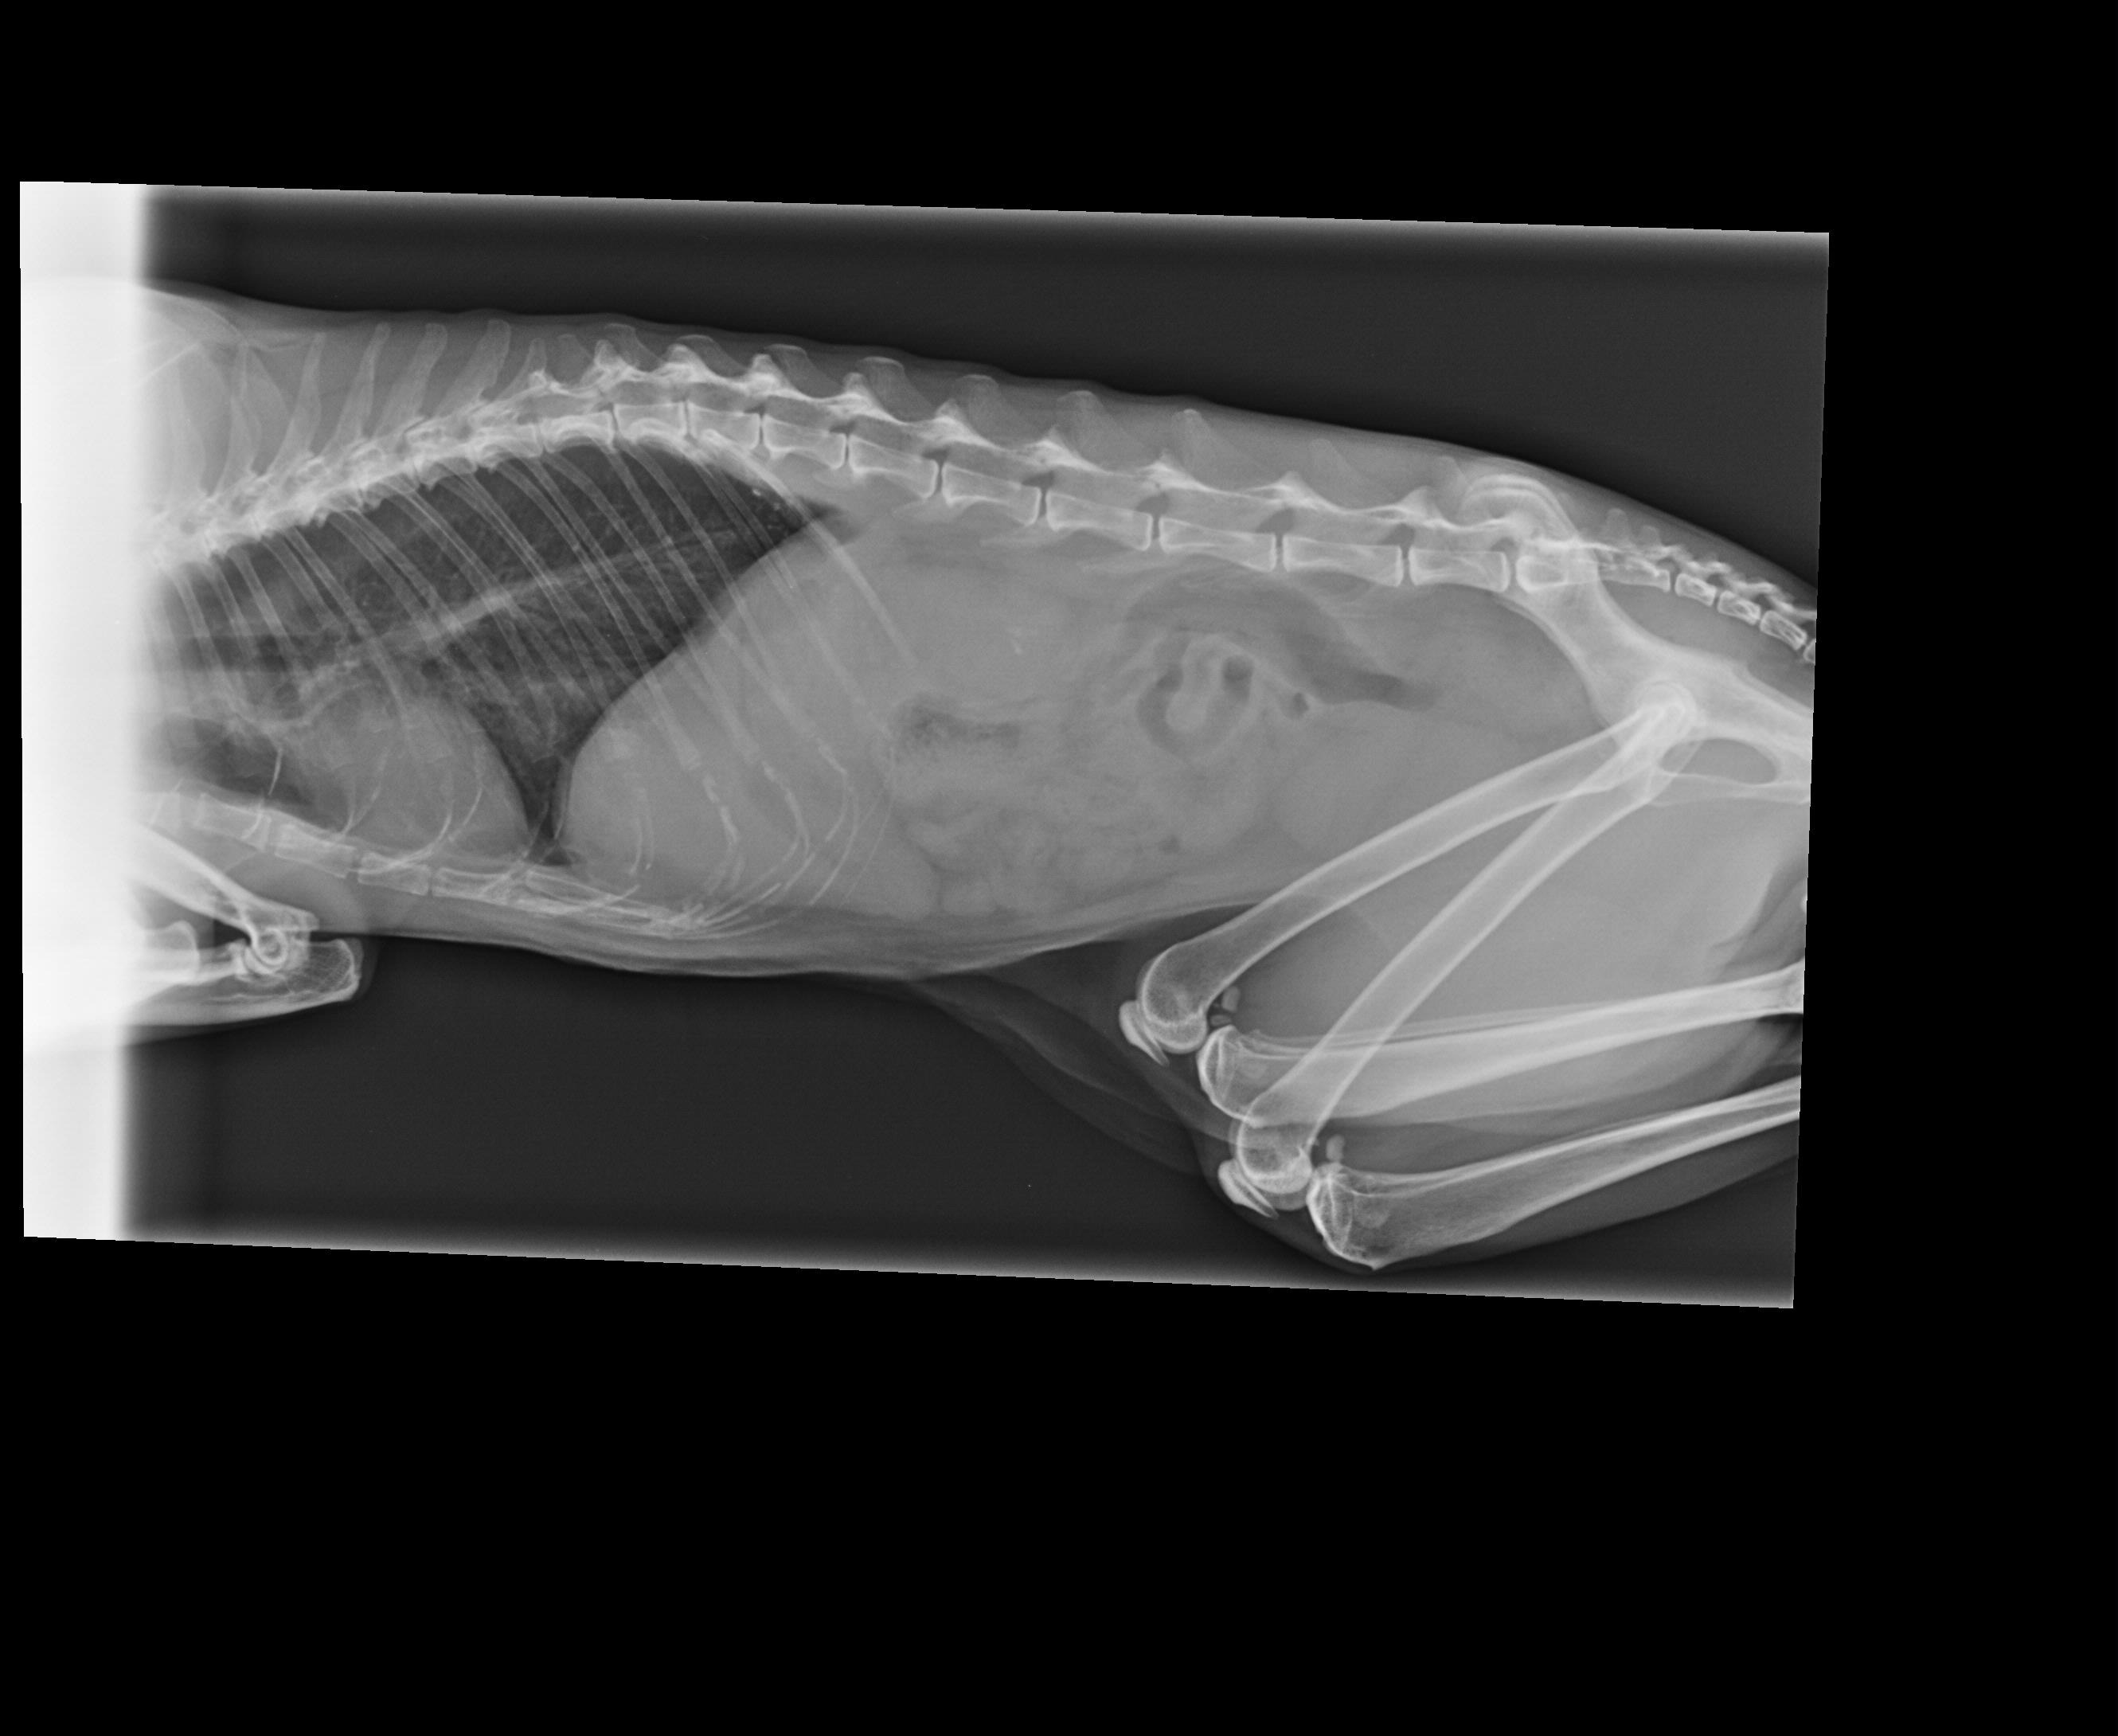

Nuestra veterinaria ordenó nuevos exámenes de laboratorio y otras radiografías. Hicimos todos los estudios, y aunque los resultados de laboratorio salieron mejor de lo que esperábamos, la doctora se dio cuenta, a través de la nueva radiografía, que Buda tiene algo que está obstruyendo su ano. Aún no se ha podido determinar qué es exactamente, y ahora nuestro querido Buda necesita estudios más específicos y mucho más costosos.

La salud de nuestro amado Buda está muy delicada en este momento. Necesitamos hacer, con extrema urgencia, una tomografía computarizada (CT Scan). Hemos llamado a muchísimos lugares, pero los presupuestos son muy altos, y lamentablemente esta vez ya no podemos cubrir estos costos por nuestra cuenta, porque en casa tenemos un Rescue-Santuario con más de 40 gatitos salvados de la calle, muchos de ellos con necesidades especiales que atendemos a diario. Además, también tenemos a nuestro perro Bebé. Por esta razón, este estudio se nos hace económicamente inalcanzable.

Con el corazón en la mano, les pedimos con toda humildad su ayuda para detener el dolor de Buda, para poder realizar este examen tan importante e imprescindible para su salud. Necesitamos saber qué tiene y, de ser necesario, realizar una cirugía lo antes posible y aplicar el tratamiento adecuado para salvarlo. Aunque aún no está confirmado, existe la sospecha de que se trate de un tumor, por los síntomas y el dolor que él está presentando.